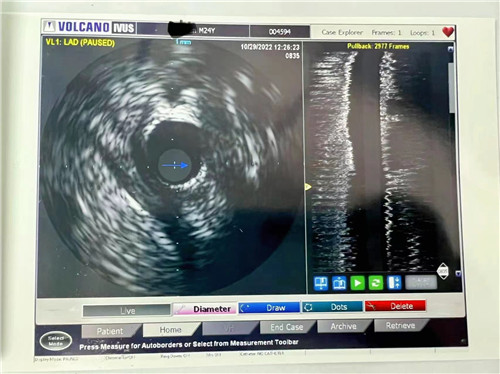

血管內(nèi)超聲提示血管斑塊負荷66.1%

小貼士:血管內(nèi)超聲(IVUS)

血管內(nèi)超聲(IVUS)是利用導管將一高頻微型超聲探頭導入血管腔內(nèi)進行探測,再經(jīng)電子成像系統(tǒng)來顯示心血管組織結(jié)構(gòu)和幾何形態(tài)的微細解剖信息。它能彌補CAG的不足之處,不僅可準確測量管腔及粥樣斑塊或纖維斑塊的大小,更重要的是可提供粥樣斑塊的大體組織信息,在顯示因介入治療所致的復雜病變形態(tài)時明顯優(yōu)于造影。